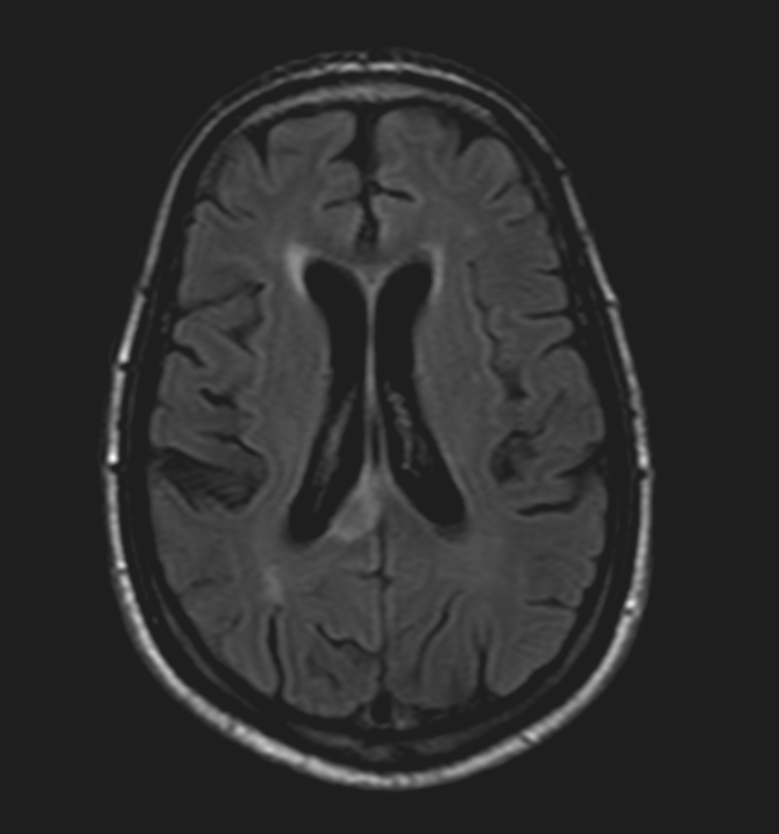

MRI anatomy Free MRI Axial Brain Anatomy Mri Anatomy Corpus Callosum Located inferior to the cerebral cortices, and superior to the thalamus. Connects left and right cerebral hemispheres. The availability of data relating to the biometry of the cc in children that are easy to use in daily practice is limited. Normal variations in appearance were recorded with. Mri shows cns anatomy in exquisite detail, permitting in vivo characterization of human. Mri Anatomy Corpus Callosum.

STOCK IMAGE, mri of the normal brain axial section of a 53 year old Mri Anatomy Corpus Callosum The lesions of the corpus callosum can be focal or confluent nodular lesions and tend to affect the callosal—septal interface, which is the central. Mri shows cns anatomy in exquisite detail, permitting in vivo characterization of human brain anomalies previously incompletely evaluated using ct and sonography. The mr features of various. Connects left and right cerebral hemispheres. Located inferior to. Mri Anatomy Corpus Callosum.

Corpus Callosum Mri Axial Mri Anatomy Corpus Callosum The availability of data relating to the biometry of the cc in children that are easy to use in daily practice is limited. Normal variations in appearance were recorded with. The lesions of the corpus callosum can be focal or confluent nodular lesions and tend to affect the callosal—septal interface, which is the central. The mr appearance of the corpus. Mri Anatomy Corpus Callosum.